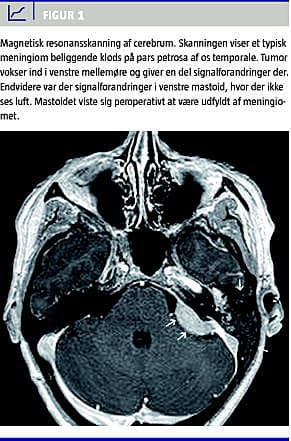

På grund af tumormistanke udførtes en computertomografi (CT) af mastoid og mellemøre, hvilket gav mistanke om en destruktiv proces i venstre mellemøre. Supplerende magnetisk resonans (MR)-skanning af mellemøre og cerebrum viste, at det drejede sig om en typisk meningiomlignende destruktiv proces langs venstre pars petrosa, der udgik fra meatus acusticus internus (Figur 1 ). Ved eksplorativ tympanotomi fandtes tumormasser i venstre mellemøre og perforation ind mod mastoidet, destruktion af den inderste del af bagerste øregangsvæg samt tegmen tympani. Biopsier af tumor viste, at det drejede sig om et meningiom. Patienten blev efterfølgende henvist til neurokirurgisk afdeling med henblik på et fælles indgreb.